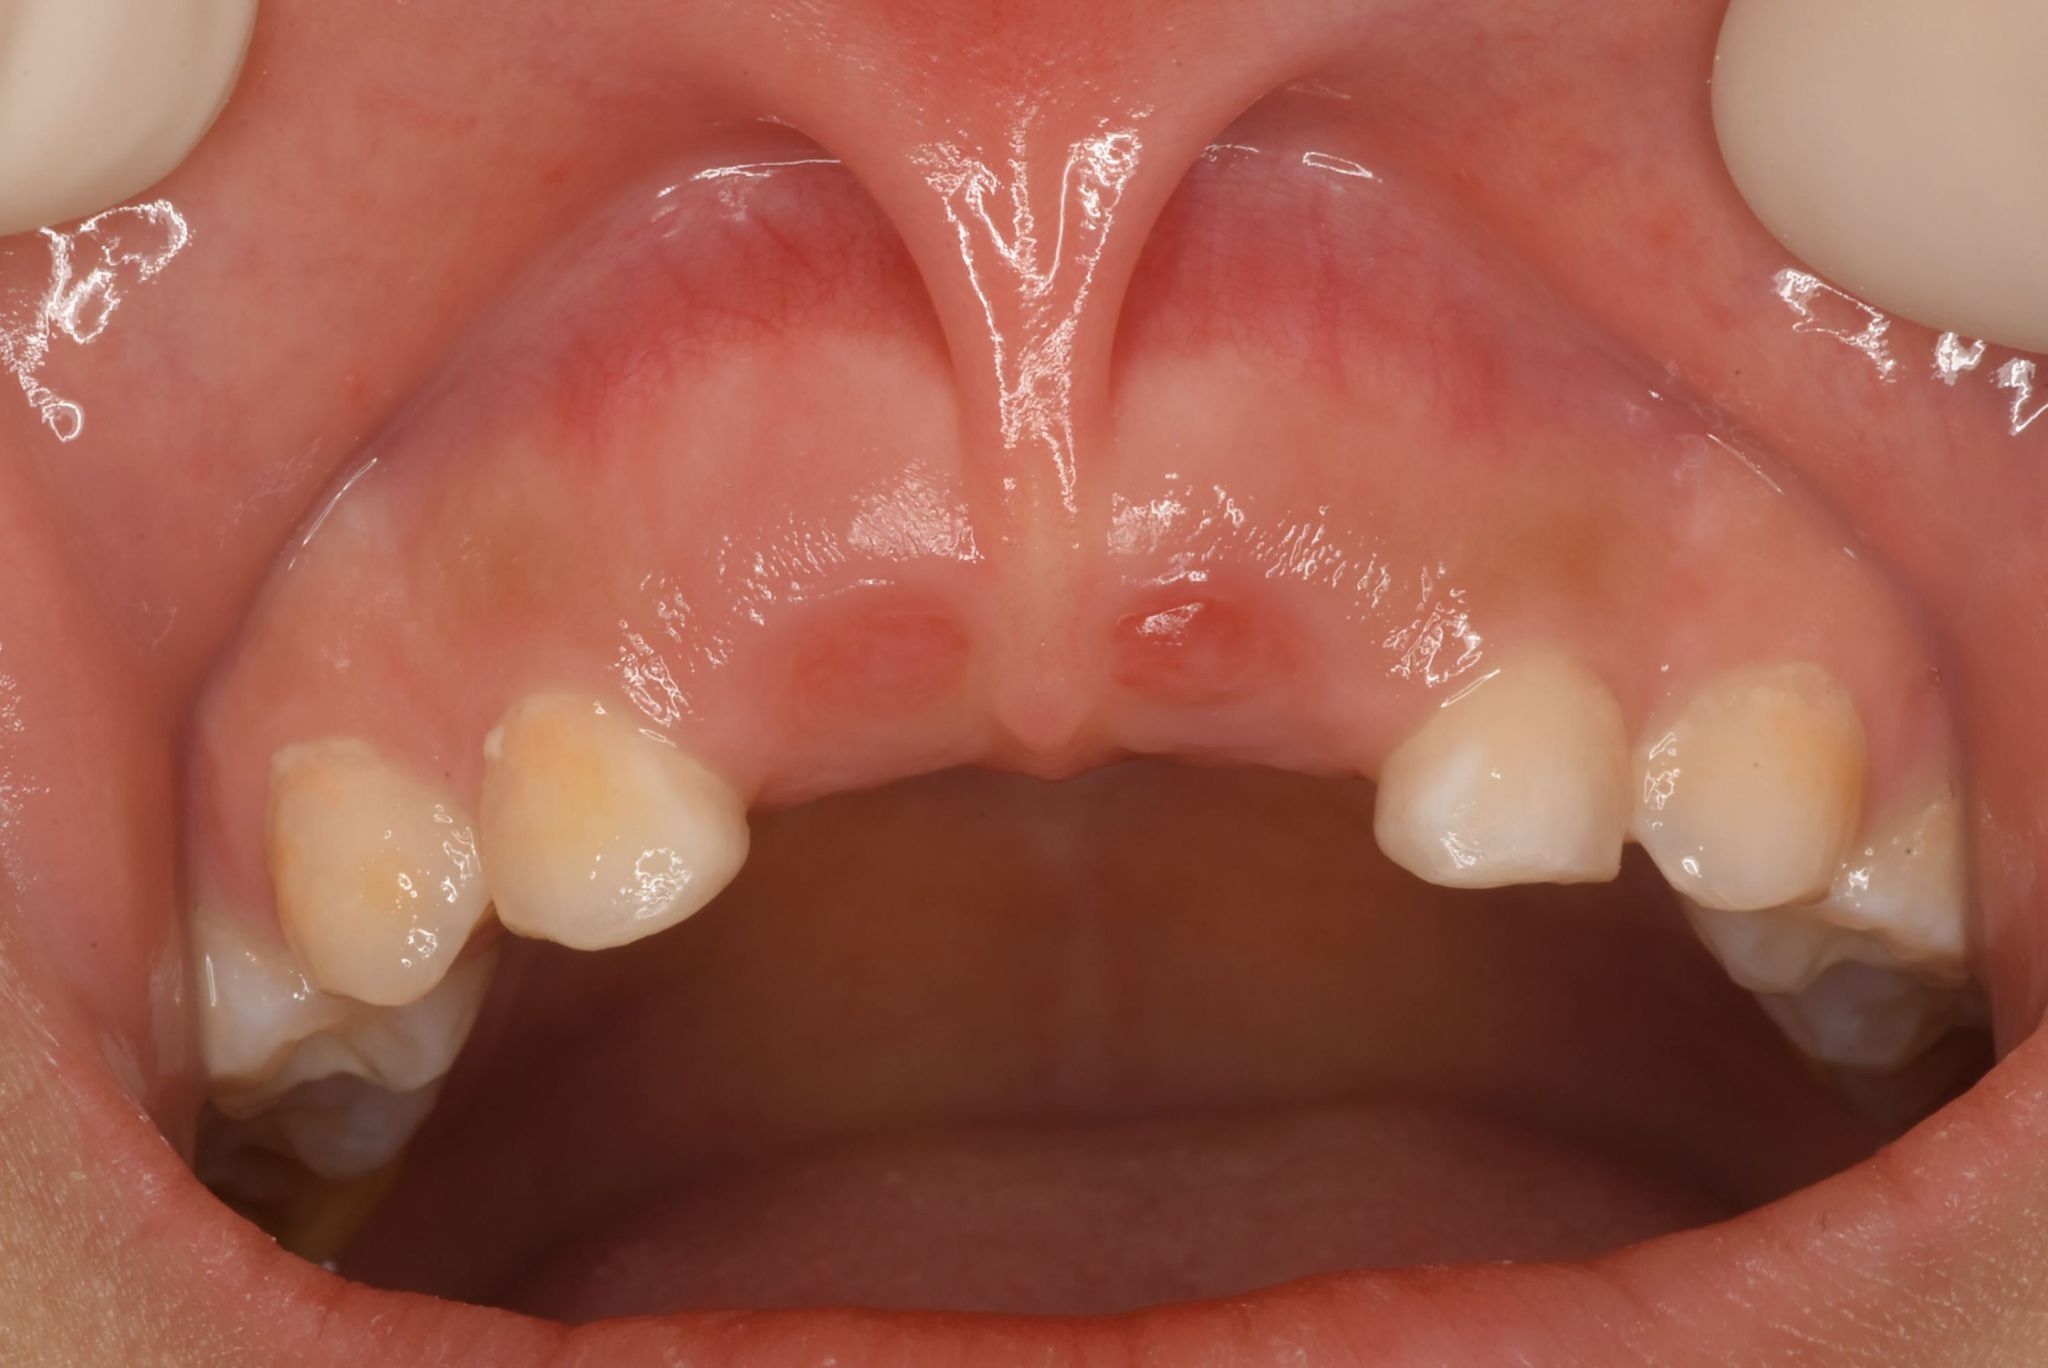

4.お子様の前歯の隙間があるけど大丈夫?すきっ歯の行く末とは

すきっ歯と言っても、すぐに治療の必要があるかというと、そうではありません。

上の3番目の歯(犬歯)が生えてくるまでの生え変わりの時期には、歯の生え方の特徴から必然的に、上の前歯がすきっ歯になるタイミングがあります。

つまり、7〜8歳のお子様の歯並びは、すきっ歯だからすぐに異常と判断するのではなく、経過観察が必要な場合もあります。

しかし、下の写真のような上唇小帯と呼ばれるヒダが、歯の並ぶスペースに大きく伸びていると、注意が必要です。

永久歯に生え変わってもヒダが邪魔をしてすきっ歯を作ってしまうことがあるので、その場合は、ヒダを切る処置が必要です。

他にも、歯の本数の不足や、逆に前歯のところに余分に歯が埋まってしまっていて、それがすきっ歯を作るケースもあります。

すきっ歯の問題は、見た目はもちろん、歯の間に食べ物がつまりやすく虫歯や歯周病のリスクを高めてしまうことや、空気が漏れて発音が不明瞭になることなどが挙げられます。